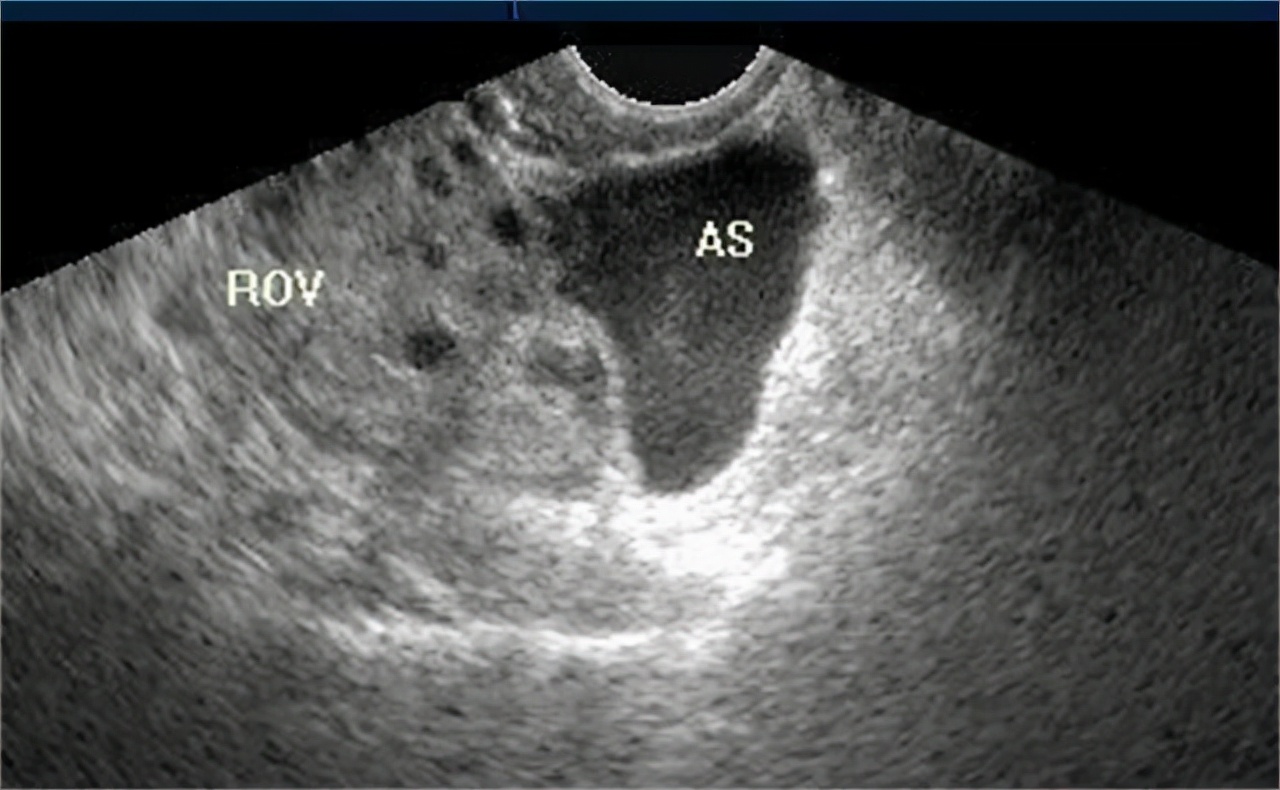

安排小姑娘做完B超和腹腔镜检查等一系列检查后,过了几个小时结果出来了,果然是 黄体破裂。

不过还好,不是很严重。 患者子宫附件有可触边界不清的包块,有轻微压痛,出血比较少,红细胞和血红蛋白值降低而且腹部积液少 ,只需要保守治疗即可。将病情同母女两讲清楚后,我建议住院治疗一周,好随时观察情况,以免后期突然病情恶化,不能及时治疗。办理完住院手续后,我让小姑娘这几天最好都 卧床休息,避免剧烈运动,多喝水,保持大便通畅 。